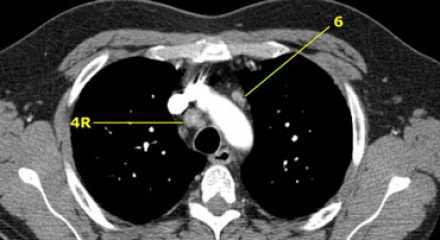

На изображении слева мы видим 4R паратрахеальные узлы. Кроме того здесь представлен узел кнаружи от дуги аорты, то есть 6 группы.

4L. Левые нижние паратрахеальные лимфатические узлы

4L узлы расположенные слева от левой стенки трахеи, между горизонтальными линиями проведенными касательно верхней стенке дуги аорты и линией проходящей через левый главный бронх на уровне верхнего края верхнедолевого бронха. Они включают паратрахеальные узлы расположенные кнутри от артериальной связки.

Узлы 5 группы (аортопульмонального окна) расположены кнаружи от артериальной связки.

На левом изображении над уровнем легочного ствола представлены нижние паратрахеальные узлы слева и справа, так же здесь представлены узлы 3 и 5 групп.

Изображение слева выше уровня карины. Слева от трахеи 4L узлы. Обратите внимание что они расположены между легочным стволом и аортой, но не в аортопульмональном окне, потому что они лежат медиальнее артериальной связки. Лимфатические узлы латеральнее легочного ствола относятся к 5 группе.